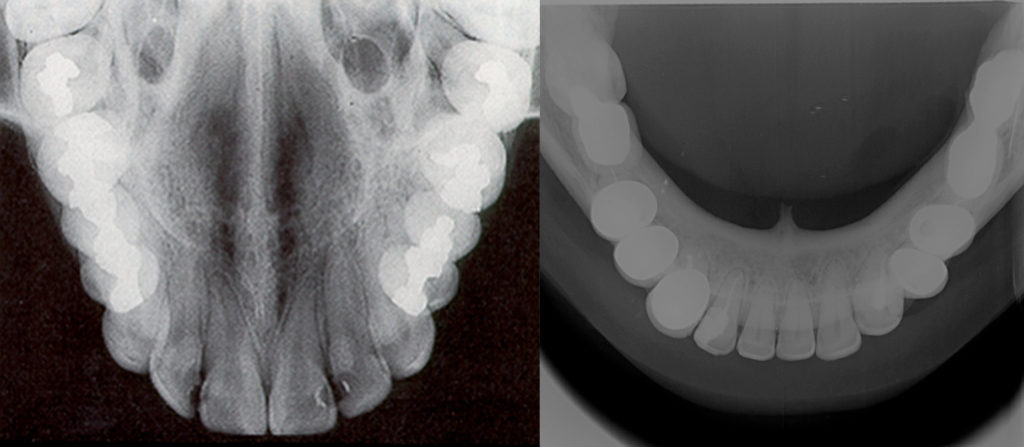

Técnicas oclusales

Así denominadas porque la colocación y sujeción de la película se realizan en el plano oclusal, entre el maxilar y la mandíbula. Pueden dividirse en superiores e inferiores. Se utilizan como complemento de los procedimientos periapicales, para estudios más amplios de áreas óseas, fracturas alveolares, palatinas o del cuerpo mandibular, límites de lesiones quísticas o tumorales, dientes incluidos, cuerpos extraños, cálculos del conducto de Wharton, etc.